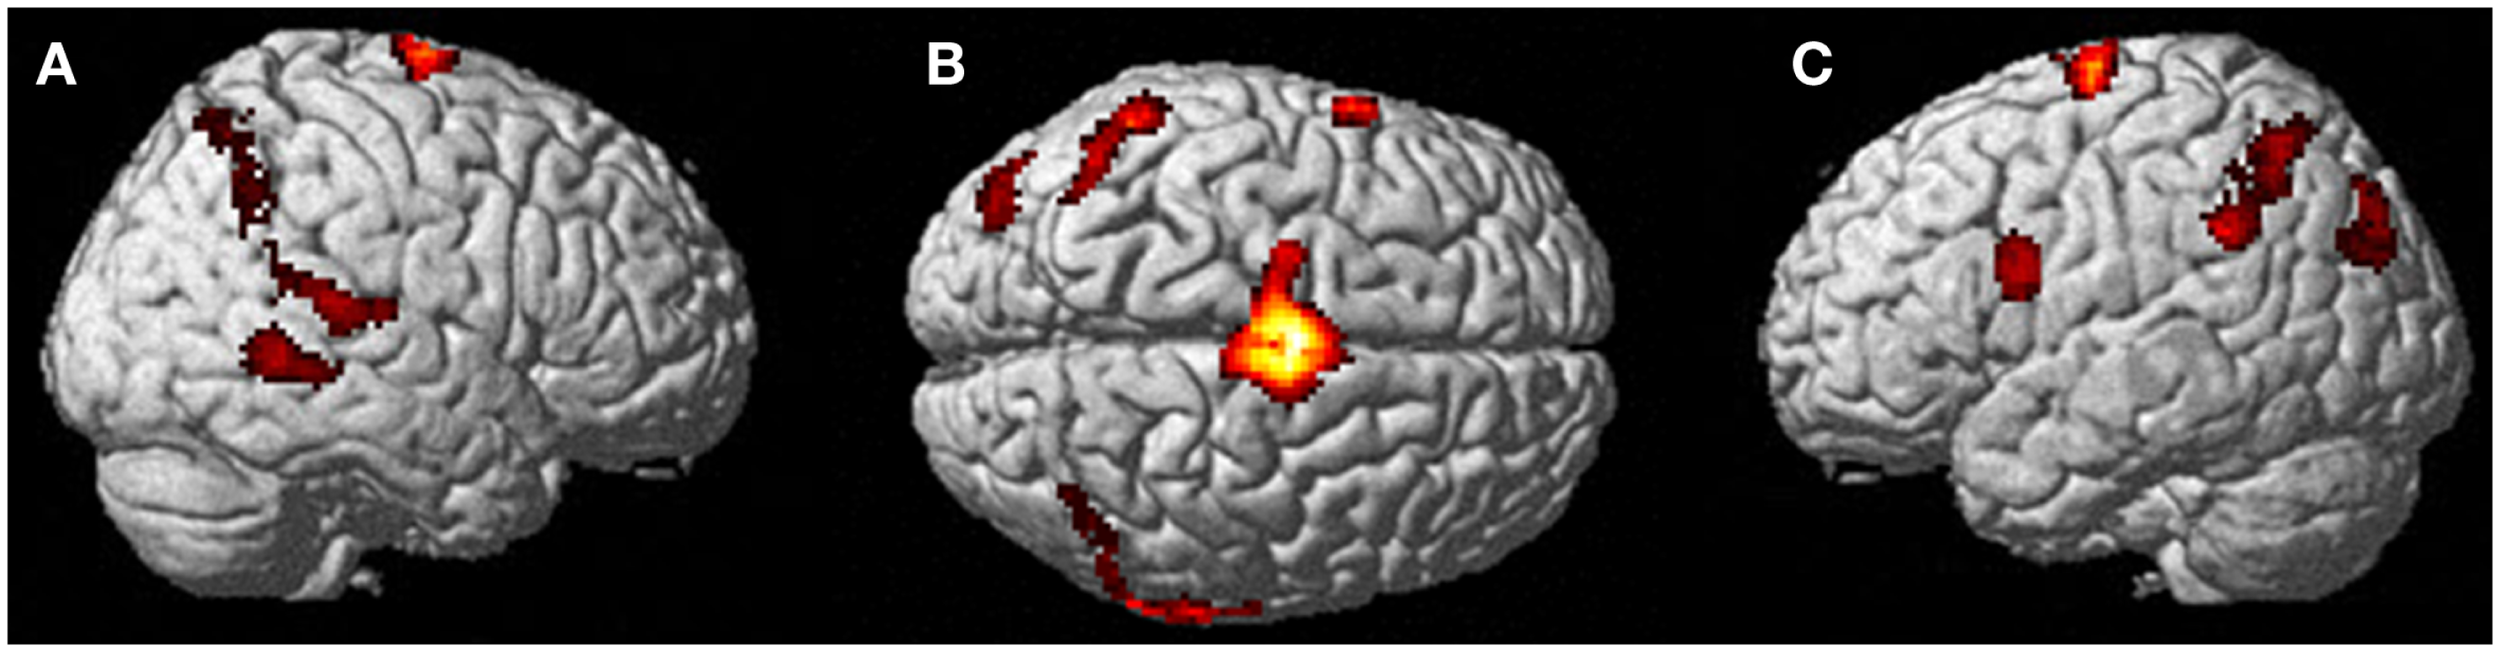

Neural activation patterns for each of these ECE Runs were analyzed separately with rest subtracted from the experience. Given the lack of significant difference between the results of each of the three Runs, all ECE Runs were combined into one analysis to increase power and observe brain regions that were concomitantly activated for each Run. Results are reported with a family wise error (FWE) very stringent correction for multiple comparisons at 0.001. Results are presented in Figure 1. The most significantly and consistently activated areas during the ECE compared to the non-ECE blocks were left lateralized in the supplementary motor area (SMA) (x, y, z = −2, −18, 62, cluster 247, T = 6.66, p = 0.001), supramarginal gyrus/posterior superior temporal gyrus (x, y, z = −64, −46, 24, cluster 60, T = 6.04, p = 0.001), inferior temporal gyrus (x, y, z = −48, −54, −20, cluster 72, T = 5.89, p = 0.001), middle and superior orbital frontal gyri (x, y, z, = −26, 56, −10, T = 5.05, p = 0.001), and the cerebellum (x, y, z = −50, −48, −30, T = 5.76, p = 0.001). The parietal and superior temporal activation taken together correspond to the temporal parietal junction. There was significantly less activation during the ECE blocks compared to non-ECE blocks (Figure 2) in bilateral posterior visual regions: the lingual gyrus (x, y, z = 14, −64, 4, cluster 19205, T = 13.23, p = 0.001) and the cuneus (x, y, z = 0, −92, 18, cluster 19205, T = 12.71, p = 0.001).

Figure 1. Rendered image of significantly activated regions of the brain while the participant was having extra-corporeal experiences. Most significantly activated regions are lateralized to the left side and include the supplementary motor area (F), the cerebellum (B,D,E), the supramarginal gyrus (D,F), the inferior temporal gyrus (B,D,F), the middle and superior orbitofrontal gyri (A,C,D,E). The p-value was set at 0.001 uncorrected for this image with the cluster threshold at 200 significant voxels.

The second control task involved the participant imagining herself performing jumping jacks and then not imagining anything and just keeping her eyes closed waiting for the next start cue for the jumping jacks. Results are presented in Figure 4. The imagining of herself performing the jumping jacks, controlling for multiple comparisons at p < 0.001, revealed significantly more activity in the posterior SMA (x, y, z = −2, −10, 60, cluster 1424, T = 7.95, p = 0.001), paracentral lobule (x, y, z = 0, −12, 68, cluster 1424, T = 6.72, p = 0.001), middle temporal gyrus (BA22) (x, y, z = 68, −48, 8, cluster 132, T = 5.72, p = 0.04), precentral gyrus (BA44) (x, y, z = −60, 6, 22, cluster 136, T = 5.11, p = 0.035), inferior parietal lobule (x, y, z = −40, −64, 58, cluster 265, T = 4.64, p = 0.001), and superior temporal gyrus (BA22) (x, y, z = 68, −34, 12, cluster 156, T = 4.78, p = 0.019). The TPJ activity was more bilateral than during the ECE runs (Figure 4). There was also less activity in bilateral cuneus (x, y, z = 6, −76, 4, cluster 22067, T = 10.16, p = 0.001) and bilateral superior orbital frontal gyrus (x, y, z = −28, 26, −28, cluster 617, T = 6.50, p = 0.001; x, y, z = 4, 48, −28, cluster 455, T = 5.69, p = 0.001) during the jumping jack imagery compared to rest.

Figure 4. Results from visualizing herself performing jumping jacks compared to rest. (A) Right hemisphere; (B) dorsal view of the SMA activity; and (C) left hemisphere activation. The p-value for this image was set to 0.001 uncorrected with the cluster threshold at 100 significant voxels.

In the third condition, we examined the brain areas involved in a whole body motor imagery to examine if the ECE was similar to motor imagery in this participant. The first general observation is that in this condition, activations tended to be bilateral as opposed to mainly left-sided activations observed in the ECE. The second observation is that the activations when the participant was told to imagine doing jumping jacks were less extensive than for the ECE. They included bilateral SMA extending into the paracentral lobule, bilateral inferior parietal lobule, right middle and superior temporal gyri, and left precentral gyrus. There was reduced activity in the cuneus bilaterally and in the superior orbital frontal gyrus also bilaterally. Activations of the SMA, inferior parietal lobule, and precentral gyrus have been reported in two previous studies of kinesthetic imagery using hand movements (Guillot et al., 2009; Szameitat et al., 2012b). ECE and whole body motor imagery were both associated with a reduction in cuneus activation (but less so for motor imagery) suggesting that visual imagery was inhibited during both conditions. During motor imagery, there was less activity in the superior orbital frontal cortex whereas there was more activity in the middle and superior orbital frontal cortex during ECE. This is suggestive of more motor monitoring during ECE than motor imagery.